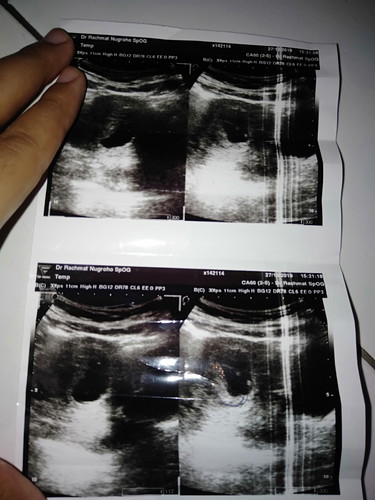

Terimakasih ya Allah sudah mempercayakan pada hamba untuk merasakan bagaimana rasanya hamil, walaupun hanya sampai 11 Minggu saja, sedih putus asa terpukul itu pasti, tapi saya yakin engko memiliki rencana yang indah untuk aku dan suamiku, Semangat ya bunda" yg lagi hamil semoga lancar sampai persalinan, Minta doanya supaya bisa di berikan kepercayaan lagi sama Allah Amin,